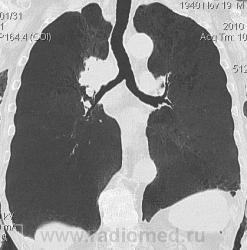

Мужчина 69 лет, с последствием ОНМК находился в доме-интернате для инвалидов. В анамнезе пневмония справа и исходом в пневмосклероз. ФЛГ не проходил 1.5 года. Анализы: СОЭ 20 мм/ч, остальное - без особенностей. Поступил в неврологическое отделение с диагнозом: повторное ОНМК. Невролог заподозрил метастазы головного мозга, направил на рентгенографию легких. После выявленых изменений в правом легком, пациент направлен на КТ головного мозга и грудной полости. От контрастирования и бронхоскопии категорически отказался.

По поводу подозрения на туберкулез пациента в прошлом нодократно проверяли, исключили. ФЛГ архива у меня нет. Все только со слов пациента. Кальцинаты в корне массивные. Трудно сказать, откуда опухоль (если это не конгломерат лимфоузлов!) плотностью 35 ед.Н - то ли из вехнедолевого бронха, который имеет культю 0.4 см и заканчивается выпуклым контуром, но при этом сохраняется воздушность почти всей доли; то ли периферический с центром в прикорневой зоне и вторичным прорастанием ВДБ. К сожалению забыла про снимок легких, на днях выставлю. Я первоначально считала периферический (верхушка, на фоне пневмосклероза) с мтс средостения. По плотности на верхушке узелок 5 ед.Н, только поэтому засомневалась, где же первичный. Лимфоузлы средостения множественные, до 2 см. Кроме того, на верхней стенке правого главного бронха есть мелкое образование такой же 35 е.Н плотности, то ли аденома, то ли прорастает... Без бронхоскопии - только гадать

это периферический рак S2 в/доли правого легкого с мтс во внутригрудные л/узлы.

А тут нечего гадать - данную демонстрацию можно поместить в учебник: узловое образование, с бугристыми, лучистыми контурами, связаное с плеврой, "дорожкой" к корню, перифокальной инфильтрацией. Корень расширен полицикличен за счет конгломерата увеличеных бронхопульмональных, трахеобронхиальных и бифуркационных л/узлов, значительно сдавливающих в/долевой бронх, с нарушением вентиляции в/доли.

Центральный рак ВДБ справа с мтс в л/узлы паратрахеальные нижние, верхние справа, БФ. МТС в головной мозг. А про печень мало сканов

Мне кажется в 6 сегменте печени мтс + еще мтс поражение левого надпочечника вероятнее всего. Мтс в нижние паратрахеальные (с обеих сторон)+бифуркационные л/у. Поражения верхних паратрахеальных не вижу (на коронарах), аксиалы - не показыны сканы выше верхнего края дуги аорты, так что я бы не говорил про поражение верхних медиастинальных лимфоузлов (хотя тут это уже не принципиально) + мтс в головной мозг. А так - центральный рак правого легкого.